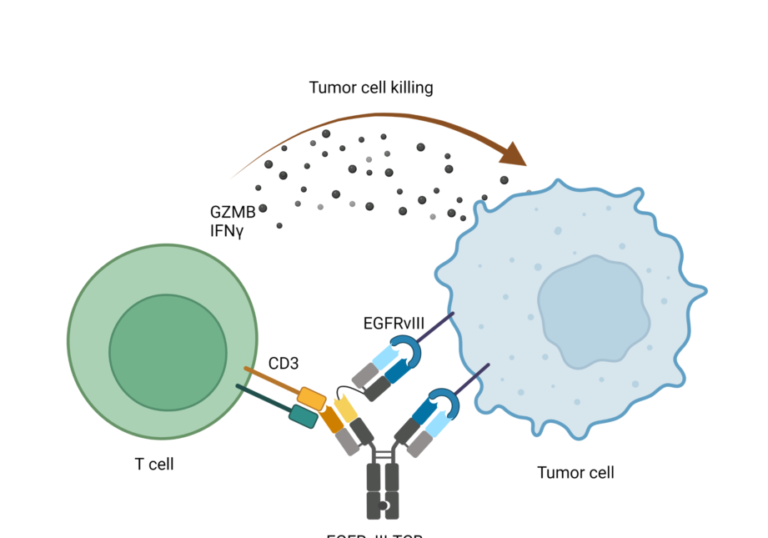

está transformando el panorama del tratamiento contra el cáncer. Estos innovadores fármacos, diseñados para reconocer simultáneamente dos...